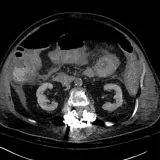

Body CT

Review cases with classic "textbook" pathology. Once you've mastered the basics, move on to practice cases with more challenging or subtle findings.

Oftentimes the key to nailing a difficult radiology case is having seen a similar case before. Practice with over 1,500 carefully selected cases covering a comprehensive list of diagnoses.

Master classic and atypical appearances of pathologies more efficiently than haphazardly reviewing cases at work. Cases include sample reports, focused discussions, annotated images, and reputable references.